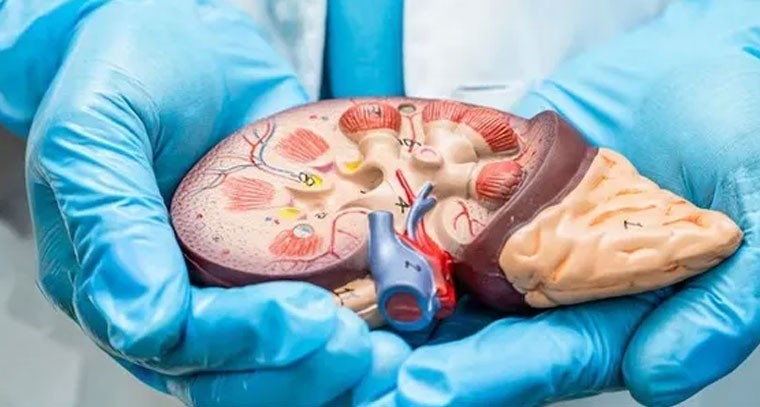

ఈ పరీక్షలతో కిడ్నీ వ్యాధి నిర్ధారణ

Publish : Thu, Mar 13, 2025, 01:03 PM